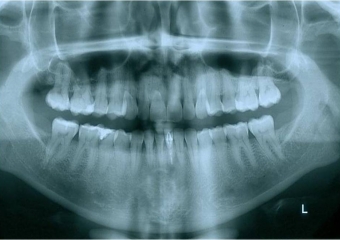

Raio x panorâmico inicial